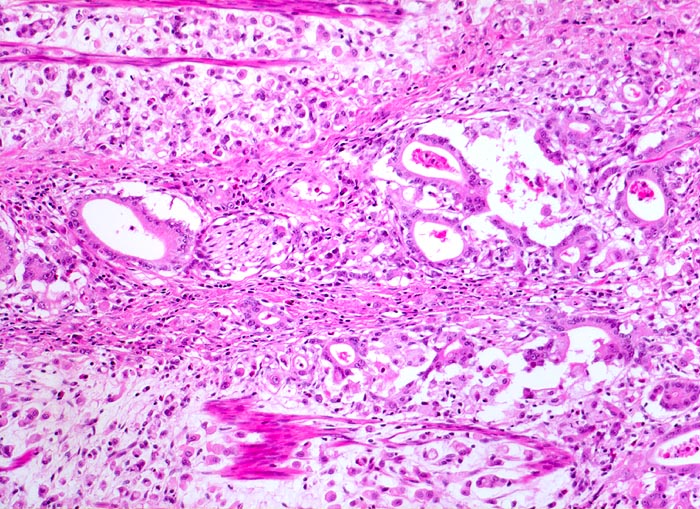

Beim diffusen Typ nach Lauren infiltrieren Einzelzellen oder Zellstränge, meist mit Siegelringzellanteilen diffus die Magenwand. Eine Drüsenbildung ist nicht erkennbar. Dieser Tumortyp tritt bei relativ jungen Patienten auf und ist mit genetischen Faktoren assoziiert (positive Familienanamnese). Wegen des diffus infiltrativen Wachstums ohne makroskopisch sicher erkennbare Grenze müssen diese Tumoren mit einem grösseren Sicherheitsabstand operiert werden. Siegelringkarzinome machen rund 20% aller Magenkarzinome aus.

Adenokarzinome können tubuläre, papilläre, muzinöse, siegelringzellige und undifferenzierte Anteile aufweisen, wobei die beiden letzteren besonders aggressive Tumoren darstellen.

• Ein Grossteil des Tumorinfiltrats besteht aus einzeln oder in kleinen Gruppen liegenden Zellen mit intrazytoplasmatischen Schleimvakuolen, die teilweise den Kern verdrängen (Siegelringzellen): diffuser Typ des Magenkarzinoms nach Lauren.

• Nur vereinzelt Drüsenbildung.